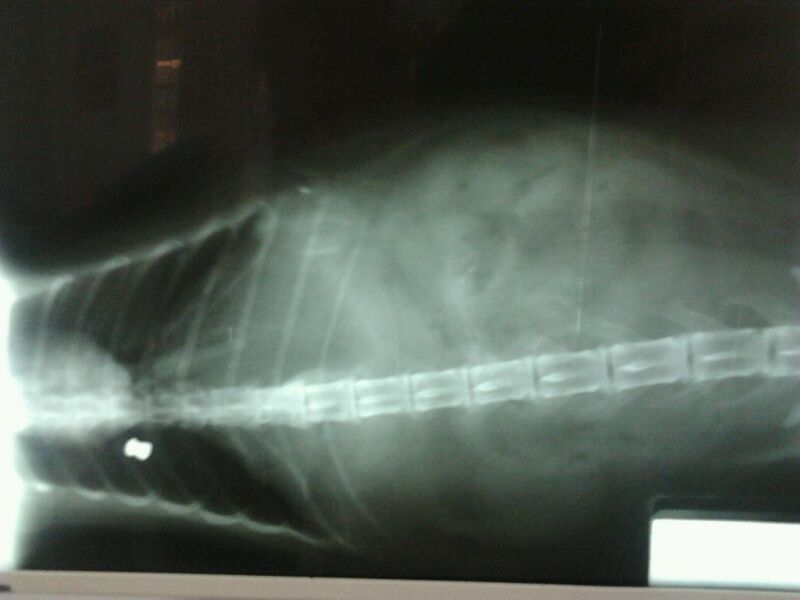

Ahora os adjuntaré las radiografías, para que veáis el balín.

Incluso ha puesto radiografías del balin. Por la penetración en el gato parece una arma potente, además no hay deformación ¿ no ?

Yo no soy nada del tipo forense o veterinario pero me atrevo a compartir con vosotros lo que me parece al ver las fotos, que nadie las tome por una opinión ni acertada ni profesional pues es solo eso, una opinión personal.

Por lo que veo en la foto, su penetración oblicua, el angulo, la deformación o ensanchamiento que se ve en la segunda y sobre todo por el resultado de muerte en el pobre gato me atrevería a asegurar que ha sido producido por una carabina.

Parece entrar en como oblicuo y con angulo descendente, como disparado desde una terraza o ventana colindante, demasiado potente en todo caso para una pistola. Una pistola dudo mucho que pueda hacer eso según sale de fabrica dada su escasa energía, la cabeza plana del perdigón unido al duro pelo del animal mas allá de unos metros solo conseguirían darle un moratón sin penetración, suficiente para producir una lesión, pero no es el caso por lo que a mi me parece.